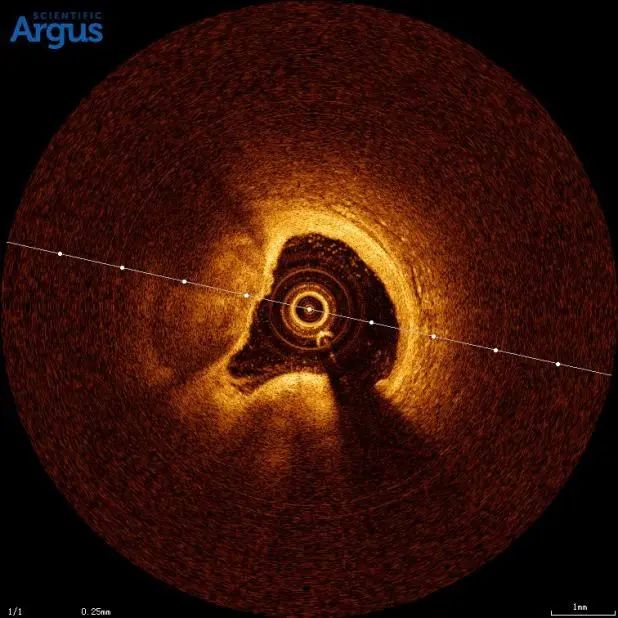

患者张先生,77岁,主因发作性胸痛、气短4天,加重2小时入院。入院诊断:冠状动脉性心脏病 急性前壁ST段抬高型心肌梗死 高血压病3级(很高危) 陈旧性脑梗死。冠脉造影显示冠脉前降支成角,迂曲,重度钙化,孙彦博教授团队在应用冠脉腔内影像学技术OCT对该血管进行了进一步的评估,结果显示:LAD近中段可见重度钙化,据此选择2.5×12mm Shockwave IVL冲击波球囊对近中段钙化病变进行4个周期的预处理,应用OCT进一步评估显示严重钙化处出现钙化断裂带,置入支架后取得很好的效果。

患者冠脉造影图像及OCT显示360°环形钙化

使用IVL血管内冲击波技术处理钙化病变 4atm 震动3个周期。OCT显示可见明显钙化断裂带。